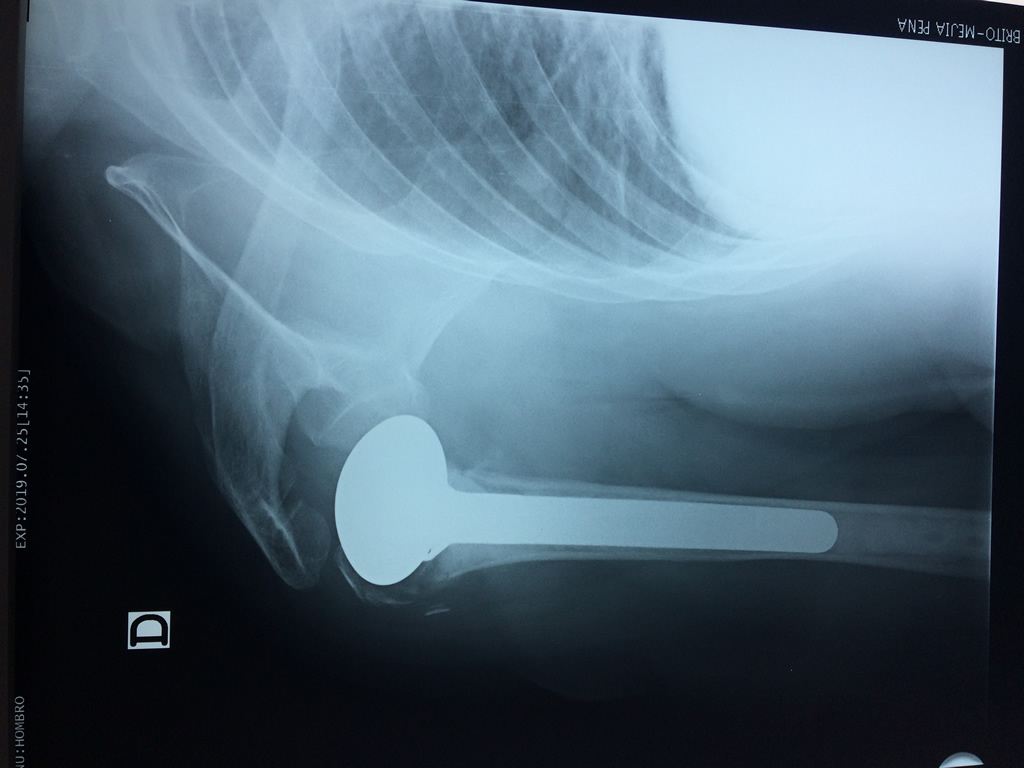

La principal articulación del hombro es la que une la cabeza del húmero con la escápula, recibe el nombre de articulación escapulohumeral y presenta dos superficies articulares, una de ellas corresponde a la cabeza del humero que tiene forma semiesférica y la otra es la cavidad glenoidea de la escápula, estas superficies están recubiertos por cartílago que permiten un movimiento suave e indoloro.

Exteriormente una envoltura de tejido blando circunda el conjunto, es la llamada cápsula articular que está reforzada por varios ligamentos que le dan estabilidad e impiden que los huesos se desplacen más allá de sus límites fisiológicos. Un conjunto de músculos y sus tendones se unen a las superficies de los huesos y hacen posible la movilidad de la articulación, entre ellos es muy importante el manguito rotador formado por cuatro músculos que proporcionan movilidad y estabilidad al hombro.